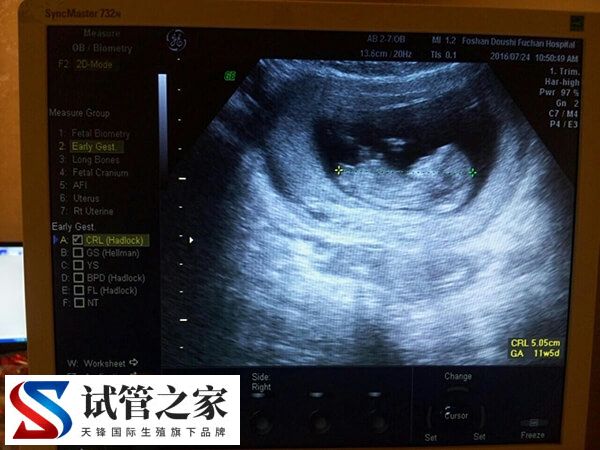

- 核实孕周、判断胚胎发育情况。根据孕囊的平均直径、胎芽大小、胎儿的头臀长判断孕龄,有助于中晚孕期间判断胎儿发育的状况。经阴道B超胎芽大于5mm时,应该见到胎心搏动。如果没有见到胎心搏动,提示有胚胎停止发育 的可能,应定期复查;